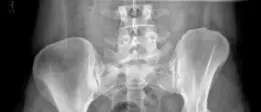

أظهر الفحص السريري لهذه المريضة: * **الأعراض:** ألم في الفخذ الأمامي للورك الأيمن مع ألم أخف في الفخذ الأيسر. * **نطاق الحركة:** * الامتداد-الثني: 0–125 درجة. * الدوران الداخلي-الخارجي: 40–60 درجة. * التبعيد-التقريب: 45–30 درجة. * **اختبارات محددة:** * **اختبار ستينشفيلد (Stinchfield test):** إيجابي، مما يشير إلى مشكلة داخل المفصل. * **اختبار الثني-التقريب-الدوران الداخلي (Flexion-Adduction-Internal Rotation test - FADIR):** إيجابي، وهو شائع في حالات تمزق الشفا أو الانحشار الفخذي الحُقي. * **العجز الرئيسي:** ألم في الفخذ الأمامي وصعوبة في المشي والنشاط البدني. * **التقييم العصبي الوعائي:** طبيعي في الأعصاب الوركي والفخذي والسدادي، ونبضات طبيعية في الشرايين الظنبوبي الخلفي والظهري للقدم. إذا كنت تعاني من أي من هذه الأعراض، فمن الضروري استشارة طبيب متخصص في جراحة العظام، مثل الأستاذ الدكتور محمد هطيف في صنعاء، لتقييم حالتك بدقة وتحديد أفضل مسار للعلاج. ## تشخيص خلل التنسج الوركي تشخيص خلل التنسج الوركي يتطلب تقييماً شاملاً يجمع بين التاريخ المرضي المفصل، الفحص السريري الدقيق، والتصوير الإشعاعي المتقدم. يمتلك الأستاذ الدكتور محمد هطيف في صنعاء الخبرة اللازمة لتحديد هذه الحالة بدقة ووضع خطة علاجية مخصصة. ### خطوات التشخيص: * **التاريخ المرضي والفحص السريري:** * يبدأ التشخيص بسؤال المريض عن الأعراض التي يعاني منها، متى بدأت، وما الذي يزيدها أو يخففها. * يقوم الأستاذ الدكتور محمد هطيف بإجراء فحص سريري لتقييم نطاق حركة الورك، والقوة العضلية، وأي علامات للألم أو عدم الاستقرار. * **اختبار ستينشفيلد (Stinchfield test):** يطلب من المريض رفع ساقه المستقيمة ضد مقاومة. الألم في الفخذ يشير إلى مشكلة داخل مفصل الورك. * **اختبار الثني-التقريب-الدوران الداخلي (FADIR test):** يتم ثني الورك وتقريبه وتدويره للداخل. الألم خلال هذا الاختبار يشير غالباً إلى انحشار الفخذي الحُقي أو تمزق الشفا، وهي حالات شائعة مع خلل التنسج. * **التقييم الإشعاعي والتصوير:** التصوير الإشعاعي هو حجر الزاوية في تشخيص خلل التنسج الوركي، حيث يوفر صوراً مفصلة لبنية العظام ويساعد في قياس زوايا محددة لتحديد مدى الخلل. ![صورة شعاعية سريرية / صورة عظام](https://hutaifortho.com/media/upload/df3bf45f-bc5a-47a1-a4fe-365e1c824cc9.png) ![صورة شعاعية سريرية / صورة عظام](https://hutaifortho.com/media/upload/d3a9e8b6-d7fa-40bb-b4fb-9d2cd29891d0.png) **صورة شعاعية أمامية خلفية للحوض (Anteroposterior X-ray view of the pelvis):** توضح هذه الصورة خللاً في تنسج الورك الثنائي، حيث يظهر نقص في تغطية رأس الفخذ الجانبية لكلا الوركين. يتم قياس زوايا محددة لتحديد شدة الخلل: * **الزاوية الجانبية للمركز والحافة (Lateral Center-Edge Angle - CEA):** تقيس مدى تغطية الحُق لرأس الفخذ من الجانب. القيم الأقل من 20-25 درجة تشير إلى خلل التنسج. في الحالة السريرية المذكورة، كانت الزاوية الجانبية للورك الأيمن 15 درجة، وللورك الأيسر 18 درجة، وكلاهما يشير إلى خلل تنسج. * **زاوية تونيس (Tonnis Angle):** تقيس ميل سقف الحُق. القيم الأعلى من 10-12 درجة تشير إلى خلل التنسج. في الحالة المذكورة، كانت زاوية تونيس للورك الأيمن 17 درجة، وللورك الأيسر 15 درجة. ![صورة شعاعية سريرية / صورة عظام](https://hutaifortho.com/media/upload/2354f626-0dff-43e0-875e-b2fe46702fba.png) ![صورة شعاعية سريرية / صورة عظام](https://hutaifortho.com/media/upload/d920609d-b8ce-497c-9e67-091b13797ce1.png) **صورة شعاعية جانبية عبر الطاولة للورك الأيسر (Cross-table lateral X-ray view of the left hip):** تظهر هذه الصورة وجود دوران أمامي للحُق الأيسر (acetabular anteversion)، مما يعني أن تجويف الحُق موجه أكثر نحو الأمام من الطبيعي. ![صورة شعاعية سريرية / صورة عظام](https://hutaifortho.com/media/upload/efaf27f1-830e-4e13-a250-0921222bfb10.png) **صورة شعاعية للمظهر الجانبي الكاذب للورك الأيسر (False profile X-ray image of the left hip):** توضح هذه الصورة نقصاً في التغطية الأمامية لرأس الفخذ. كانت الزاوية الأمامية للمركز والحافة (Anterior CEA) 17 درجة، مما يؤكد نقص التغطية الأمامية. الورك الأيمن أظهر نقصاً مشابهاً في التغطية الأمامية. * **التصوير بالرنين المغناطيسي (MRI):** يمكن استخدامه لتقييم الأنسجة الرخوة مثل الشفا والغضروف، وتحديد وجود تمزقات أو تلف. من خلال هذه التقييمات الشاملة، يتمكن الأستاذ الدكتور محمد هطيف من وضع تشخيص دقيق لخلل التنسج الوركي وتحديد أفضل مسار علاجي، سواء كان ذلك علاجاً غير جراحي أو جراحة قطع العظم حول الحُق. ## عملية قطع العظم حول الحُق (PAO): حل فعال لآلام الورك عملية قطع العظم حول الحُق (Periacetabular Osteotomy - PAO) هي إجراء جراحي متقدم يحافظ على مفصل الورك، ويُعد حلاً جذرياً لمرضى خلل التنسج الوركي. تهدف هذه الجراحة إلى إعادة توجيه تجويف الحُق في الحوض لزيادة تغطية رأس الفخذ، مما يقلل الضغط غير الطبيعي على المفصل ويمنع تطور التهاب المفاصل التنكسي المبكر. بفضل خبرته الواسعة ودقته الجراحية، يُعتبر الأستاذ الدكتور محمد هطيف الرائد في إجراء هذه العمليات المعقدة في صنعاء. ### ما هي عملية قطع العظم حول الحُق (PAO)؟ عملية قطع العظم حول الحُق هي جراحة معقدة تتضمن قطع العظم حول تجويف الحُق في الحوض. يتم فصل جزء من الحُق عن بقية عظم الحوض، ثم يُعاد تدويره وتوجيهه في وضع أفضل يوفر تغطية أكبر لرأس الفخذ. بعد إعادة التوجيه، يتم تثبيت الجزء المعاد توجيهه بمسامير خاصة. هذه العملية تحسن ميكانيكا المفصل، تخفف الألم، وتزيد من نطاق الحركة، وتحافظ على المفصل الطبيعي للمريض، مما يؤجل أو يلغي الحاجة إلى استبدال مفصل الورك الكلي في المستقبل. ### متى يوصى بعملية قطع العظم حول الحُق؟ تُعد عملية PAO خياراً علاجياً ممتازاً للمرضى الذين يعانون من: * **خلل التنسج الوركي symptomatic Hip Dysplasia):** وهو السبب الرئيسي لإجراء هذه الجراحة، خاصة عندما يكون مصحوباً بألم وتلف في الشفا. * **الدوران الخلفي للحُق المعزول (Isolated Acetabular Retroversion):** وهي حالة يكون فيها تجويف الحُق موجهاً للخلف أكثر من اللازم، مما يسبب الانحشار. * **المرضى الشباب:** الذين لا يعانون من تآكل كبير في الغضروف أو التهاب مفاصل متقدم. الهدف هو الحفاظ على المفصل الطبيعي لأطول فترة ممكنة. * **فشل العلاج غير الجراحي:** عندما لا تستجيب الأعراض للعلاج الطبيعي، الأدوية، أو الحقن. ### لماذا تختار PAO بدلاً من البدائل الأخرى؟ * **الحفاظ على المفصل (Joint Preservation):** على عكس استبدال مفصل الورك الكلي، تحافظ PAO على مفصل المريض الطبيعي، مما يوفر إحساساً طبيعياً بالورك ويجنب مخاطر ومضاعفات المفاصل الاصطناعية. * **تصحيح متعدد الاتجاهات (Multidirectional Correction):** تسمح العملية بإعادة توجيه الحُق في عدة اتجاهات (أمامية، جانبية، إنسية)، مما يوفر تصحيحاً دقيقاً ومخصصاً لخلل التنسج. * **استقرار العمود الخلفي (Posterior Column Stability):** تبقى العمود الفقري الخلفي للحوض سليماً، مما يحافظ على استقرار الحوض ويسمح بتحميل جزئي للوزن بعد الجراحة. * **معالجة الأمراض داخل المفصل (Addressing Intra-articular Pathology):** يمكن إجراء تنظير مفصلي أو فتح المفصل في نفس الوقت لمعالجة أي مشاكل داخل المفصل مثل تمزق الشفا أو آفات CAM. الأستاذ الدكتور محمد هطيف، بخبرته الطويلة في صنعاء، يولي اهتماماً خاصاً لتقييم كل حالة بدقة وتحديد ما إذا كانت عملية PAO هي الخيار الأفضل للمريض، مع الأخذ في الاعتبار عمر المريض، شدة خلل التنسج، وحالة الغضروف. ### التحضير لعملية قطع العظم حول الحُق يتضمن التحضير لعملية قطع العظم حول الحُق تخطيطاً دقيقاً لضمان أفضل النتائج الممكنة. يعتمد الأستاذ الدكتور محمد هطيف على نهج شامل يشمل التقييم السريري والإشعاعي المكثف. * **التشخيص الدقيق:** يتم تأكيد تشخيص خلل التنسج الوركي الثنائي المصحوب بأعراض، كما يتضح من الصور الشعاعية (مثل Figs. 1.26, 1.27, and 1.28) التي تظهر نقص تغطية رأس الفخذ. * **خيارات العلاج الممكنة:** تتم مناقشة خيارات العلاج مع المريض، والتي قد تشمل: * **العلاج غير الجراحي المستمر:** مثل العلاج الطبيعي وتعديل الأنشطة. * **احتمالية استبدال مفصل الورك الكلي في المستقبل:** خاصة إذا كان هناك تآكل غضروفي كبير. * **طريقة العلاج المختارة:** في الحالات التي يكون فيها خلل التنسج هو السبب الرئيسي للألم، يتم اختيار عملية قطع العظم حول الحُق (PAO) على مراحل لكلا الوركين. فمثلاً، يتم علاج الجانب الأيمن أولاً بعملية PAO مع فتح مفصل لإزالة جزء من الشوكة الحرقفية الأمامية السفلية (anterior inferior iliac spine trimming). وبعد ثلاث سنوات، يتم علاج الورك الأيسر بدمج تنظير مفصلي للورك لمعالجة تمزق الشفا وتصحيح الغضروف الحُقي والفخذي، بالإضافة إلى PAO لتصحيح خلل التنسج. * **اختيار الغرسات:** يتم اختيار مسامير كبيرة بحجم 4.5 مم لتثبيت القطعة العظمية بعد إعادة توجيهها. * **الصعوبات المتوقعة واستراتيجيات التغلب عليها:** * **الصعوبة الأولى:** تحقيق قطع عظمي كافٍ لتمكين تحريك قطعة الحُق بشكل كامل في جميع المستويات. * **الاستراتيجية:** التأكد من إتمام قطع العظام في عظم الإسك (ischium)، العانة (pubis)، والحرقفة (ilium). يجب أن تكون قطعة الحُق قابلة للتحريك بسهولة في جميع المستويات دون الحاجة لقوة كبيرة. أكثر المواقع التي تحتاج اهتماماً إضافياً هي نقطة التقاء القطع الإسكي مع العمود الخلفي. * **الصعوبة الثانية:** تصحيح التشوه بشكل كافٍ لمعالجة نقص تغطية رأس الفخذ الأمامية والجانبية. * **الاستراتيجية:** يتم التصحيح باستخدام دبوس شانز (Schanz pin) في الجزء الحرقفي من قطعة الحُق. كما تستخدم خطافات العظام في قطع العانة لضمان تحرير كامل لقطعة العانة دون أي تضييق، مما يسمح بتدوير القطعة لزيادة التغطية الجانبية دون التسبب في دوران خلفي غير مقصود. ثم يتم إعادة وضع القطعة مع تمديد طفيف، ودوران داخلي، وتوسيط إنسي. من المهم فهم أن هذا التصحيح يختلف عن عمليات PAO العكسية لحالات الدوران الخلفي للحُق. يتم تثبيت القطعة مؤقتاً بدبابيس ستينمان (Steinmann pins) بحجم 3.2 مم، ويتم تقييم التصحيح بعناية باستخدام التنظير الفلوروسكوبي داخل الجراحة، مع الحصول على صورة أمامية خلفية كافية وصورة مظهر جانبي كاذب معدلة. * **الصعوبة الثالثة:** تجنب التصحيح الزائد للحُق، والذي قد يؤدي إلى انحشار فخذي حُقي أمامي وتقليل ثني المريض ودورانه الداخلي. * **الاستراتيجية:** يتم تقييم نطاق حركة المريض قبل الجراحة (ROM) في الثني والدوران الداخلي أثناء التخدير، ومقارنته بنطاق الحركة بعد تصحيح التشوه والتثبيت المؤقت للقطعة. ### تفاصيل الإجراء الجراحي لقطع العظم حول الحُق تُعد عملية قطع العظم حول الحُق إجراءً جراحياً دقيقاً ومعقداً يتطلب خبرة جراحية عالية. يقوم الأستاذ الدكتور محمد هطيف بتطبيق بروتوكولات جراحية صارمة ---